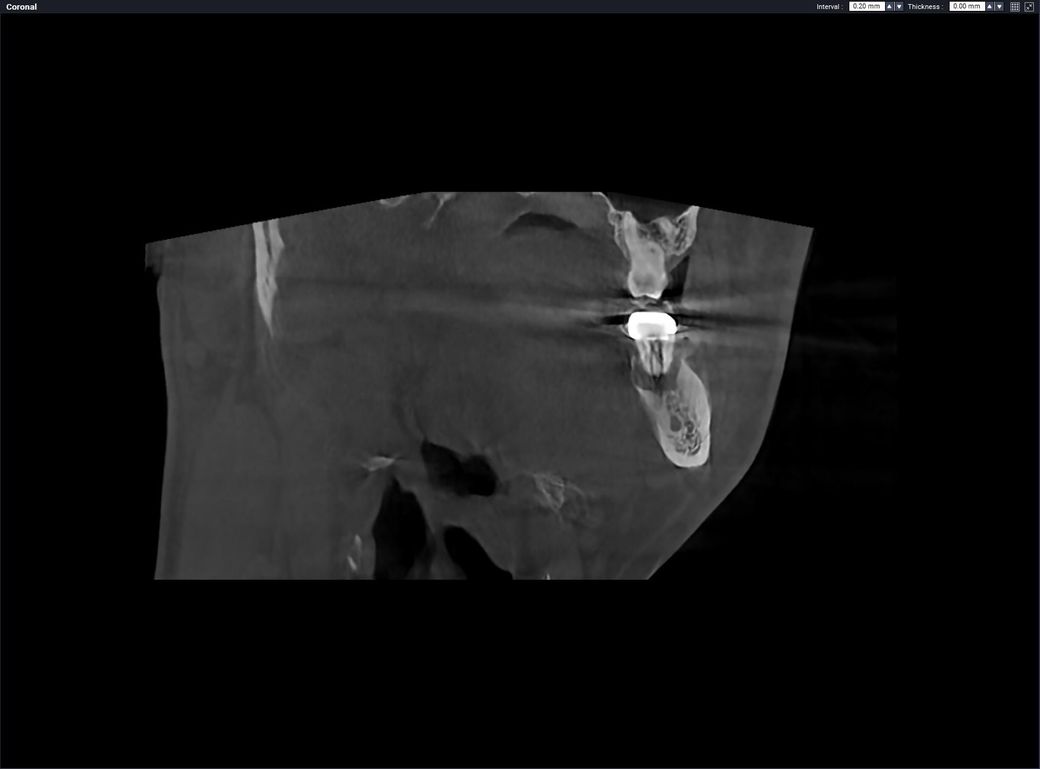

왼쪽 아래 끝에 어금니 자리입니다. X-ray사진으로 지대주까지 설치된 곳입니다.

• 1번 째 사진